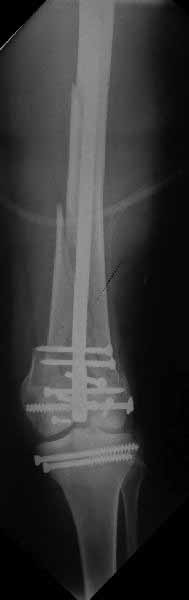

использовать. В приложении пример недавней операции, C3, открытая

репозиция, фиксация мыщелков спицами и винтами, ретроградный синтез

большеберцовым гвоздем 10,5 мм диаметром, винты 5 мм.